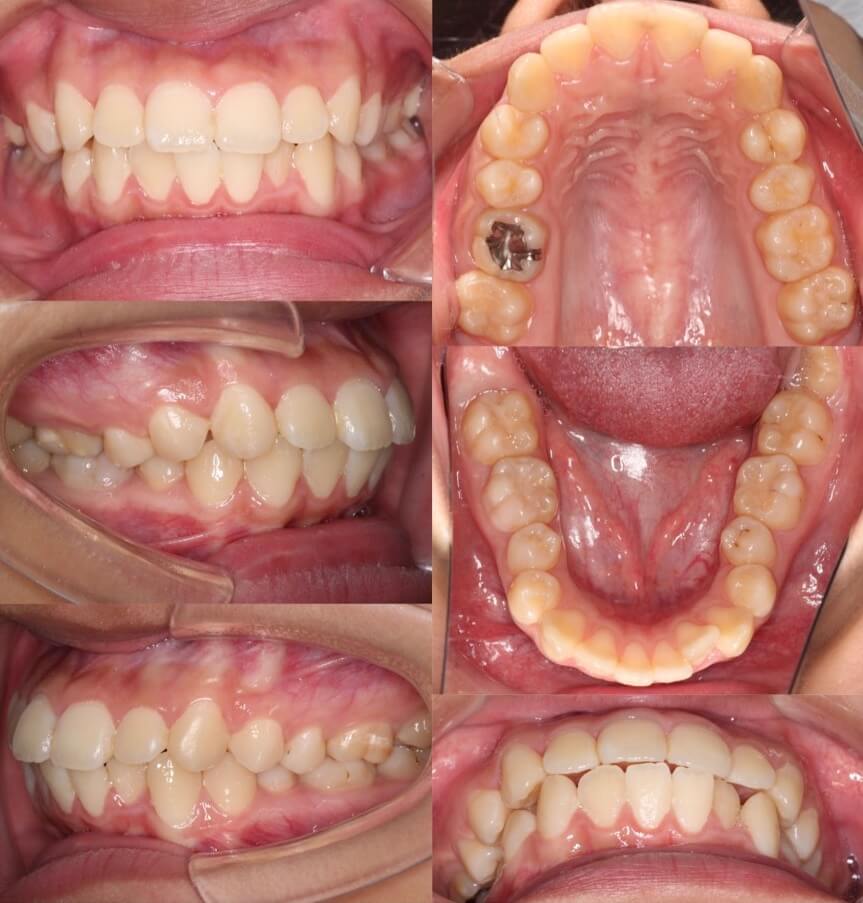

「マウスピースの後方移動の限界」

20代女性・マウスピース型装置・下あご後退型

奥歯の固定が弱いマウスピース型矯正装置の場合は、ワイヤー型矯正と比較して若干、前歯の引っ込む量が少なくなります。ですが、患者さんの希望する治療のゴールによっては、このように問題なく改善は見込めます。

<症例概要> 難易度:★★★★★

主訴:横顔で口が前に出ている

年齢・性別:20代女性

住まい:千葉県佐倉市

症状:下顎後退・上下顎前歯唇側傾斜

治療方針:抜歯空隙の閉鎖(中等度固定)

治療装置:マウスピース型矯正装置(アライナー装置)

抜歯:上下顎第一小臼歯

治療期間:2年2か月

アライナー枚数:55+33+21ステージ

リテーナー:上下クリアタイプ+フィックスタイプ

治療費用:990,000(税込)

代表的副作用:痛み・治療後の後戻り・歯根吸収・歯髄壊死・歯肉退縮

【治療シミュレーション】

上下の抜歯スペースに犬歯から順番に移動させる治療計画です。奥歯のかみ合わせが悪くならないようゴムをかけてもらうようにしています。